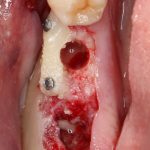

Я зафиксировал костный блок практически без адаптации на несколько винтов. Обрати внимание, что винты находятся в зоне, где не планируется установка имплантатов. Фиксация должна быть надежной, поскольку мне еще предстояла подготовка лунок для имплантатов. Трех винтов для этого вполне достаточно.

Дальнейшая адаптация костного блока свелась к сглаживанию острых краев. После чего я приступил к подготовке лунок и установке имплантатов.

Глянем на то, что получилось:

Осталось адаптировать костный блок (убрать острые края), проверить его фиксацию и, при необходимости, добавить винты. Десятисекундное дело.